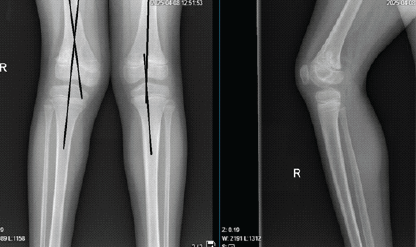

X-ray was advised, and findings were suggestive of a Salter–Harris type II fracture at the right distal femur (Fig. 2).

Figure 2: Pre-operative X-ray – anteroposterior and lateral views.

Figure 5: Post-operative check X-ray – anteroposterior and lateral view.

He was followed up in the outpatient department at 2 weeks, 6 weeks, 2 months, 3 months, 6 months, and 1 year postoperatively. At the end of 2 months, the K-wires and slab were removed with gentle knee bending exercises. At 3 months, a repeat X-ray was obtained, which showed satisfactory union (Fig. 6).

Figure 6: X-ray right knee anteroposterior and lateral view at the end of 3 months.

Gradual weight bearing was allowed with physiotherapy for gait training. Patient was independently ambulating at the end of 3 and a half months. At the end of the 6-month follow-up, he is comfortably bearing weight (Fig. 7), squatting (Fig. 8) with a good range of motion (Fig. 9), and no apparent angular deformity or limb length discrepancy clinically. At the end of the 1-year follow-up, though the range of movements was normal, there was an evident valgus deformity clinically (Fig10), and at the distal femur 8° of valgus was measured on the radiograph (Fig 11) .

Figure 11: Radiograph showing genu valgus deformity at the right knee.

Knee injuries are common among children, but fractures involving the distal femoral and proximal tibial growth plates are relatively uncommon [5]. These physeal fractures typically occur in children aged 9–14 [6]. As children grow, the epiphysis becomes less cartilaginous, and the secondary ossification center enlarges, making the epiphysis more rigid and less capable of absorbing energy. Consequently, forces are more likely to affect the physis, leading to a shift in the distribution of fractures, with most physeal knee fractures occurring after the age of 10 [7,8]. The most frequent type of injury is fractures of the distal femoral growth plate, followed by fractures of the proximal tibial growth plate. Since the majority of longitudinal growth occurs around the knee, particularly at the distal femur and proximal tibia, careful reduction and fixation are essential to avoid further damage to the growth plate, even with proper treatment, a significant risk of leg length discrepancies and angular deformities remains, necessitating close follow-up for at least 2 years [9]. In our case, we followed the child closely with clinical examinations and repeated radiographs, and at 1 year of follow-up, a valgus deformity of about 8° was noted. We have a further plan to monitor the child 6-monthly for another year and carry on further investigations to confirm a physeal bar formation, and go for its resection. The Salter–Harris classification system is used to categorize fractures in children based on the involvement of the physis, metaphysis, and epiphysis, which is important for determining both prognosis and treatment [10,11]. In this case, the fracture was classified as Salter–Harris Type II with a Thurston–Holland fragment, although the size of the fragment has little impact on the outcome [12]. Another key determinant of deformity following distal femoral physeal injury is the magnitude of displacement [13]. In our case, the displacement was significant, with a displacement in both radiographic views of >50% of the transverse diameter of the distal femoral metaphysis. For acute fractures, initial treatment involves a closed reduction and fixation under appropriate anesthesia. Salter–Harris Types I and II fractures that present 7–10 days after injury should allow for more leniency in accepting fracture displacement to avoid further injury to the physis [14]. In our case, the patient presented on the same day of injury and was taken up for closed reduction and fixation.